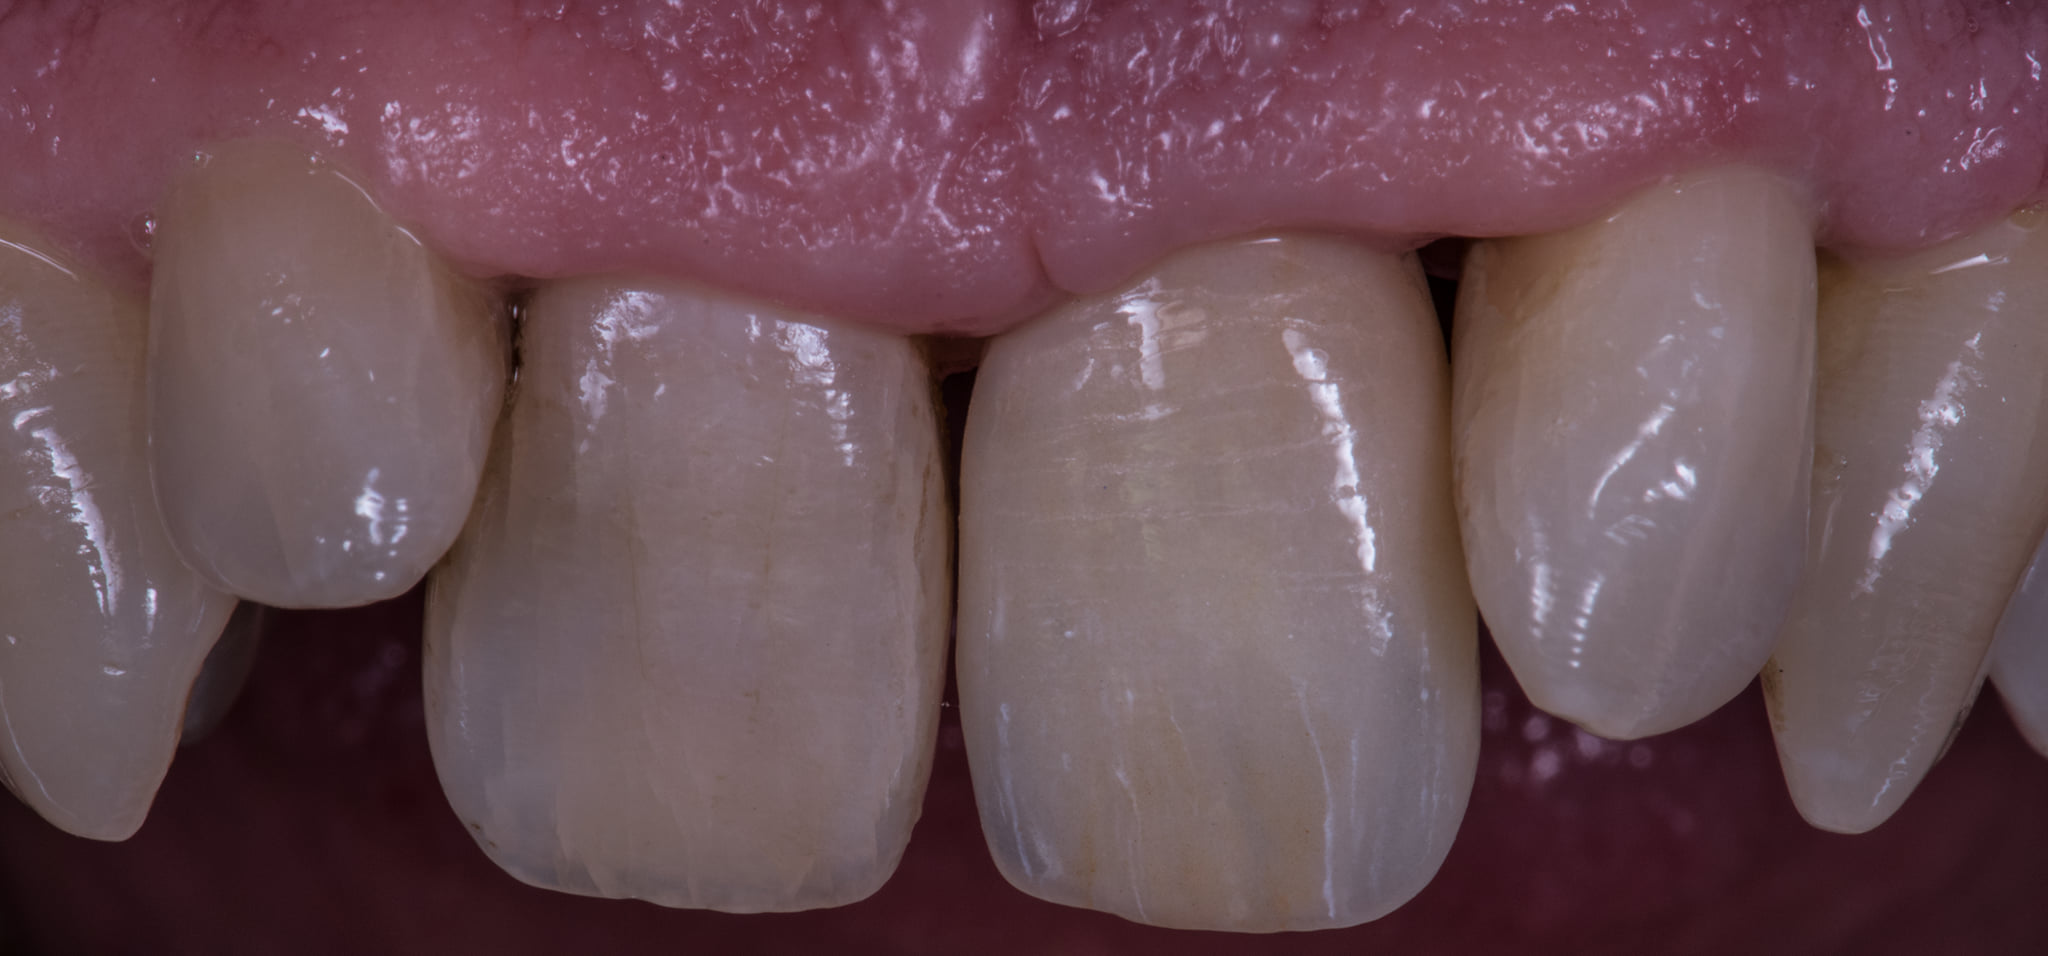

Oggi però abbiamo una soluzione che ci permette di consegnare questa corona avvitata al nostro paziente portando il foro di emergenza del canale di avvitamento dalla parte palatale. Lì potrà essere agevolmente chiuso in composito senza compromessi estetici.

Ecco quindi che l’unico motivo che poteva giustificare una protesi cementata su impianti viene miseramente a cadere!!